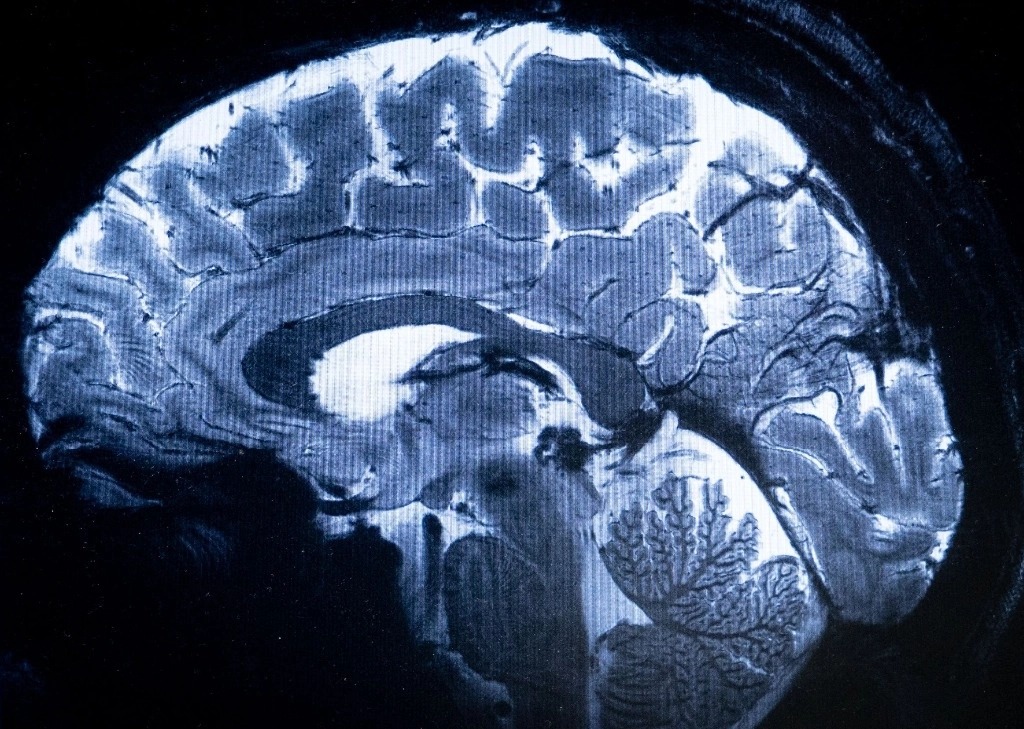

Escáner de resonancia magnética más potente del mundo muestra primeras imágenes del cerebro humano

El escáner de resonancia magnética (IRM) más potente del mundo ha logrado digitalizar con un nivel de precisión desconocido el cerebro humano, anunciaron sus responsables en Francia, una proeza que podría ser decisiva para detectar enfermedades.

"Hemos visto un nivel de precisión nunca antes alcanzado en el CEA", dijo Alexandre Vignaud, un físico que trabaja en el proyecto.

El campo magnético creado por el escáner es de 11.7 teslas, una unidad de medida nombrada en honor del inventor Nikola Tesla.

Esta potencia permite que la máquina escanee imágenes 10 veces más precisas que los IRM comúnmente utilizados en hospitales, cuya potencia normalmente no supera los tres teslas.

En una pantalla de computadora, Vignaud comparó imágenes tomadas por este poderoso escáner, apodado Iseult, con las de un IRM normal.

"Con esta máquina podemos ver los pequeños vasos que alimentan la corteza cerebral, o detalles del cerebelo que eran casi invisibles hasta ahora", dijo.